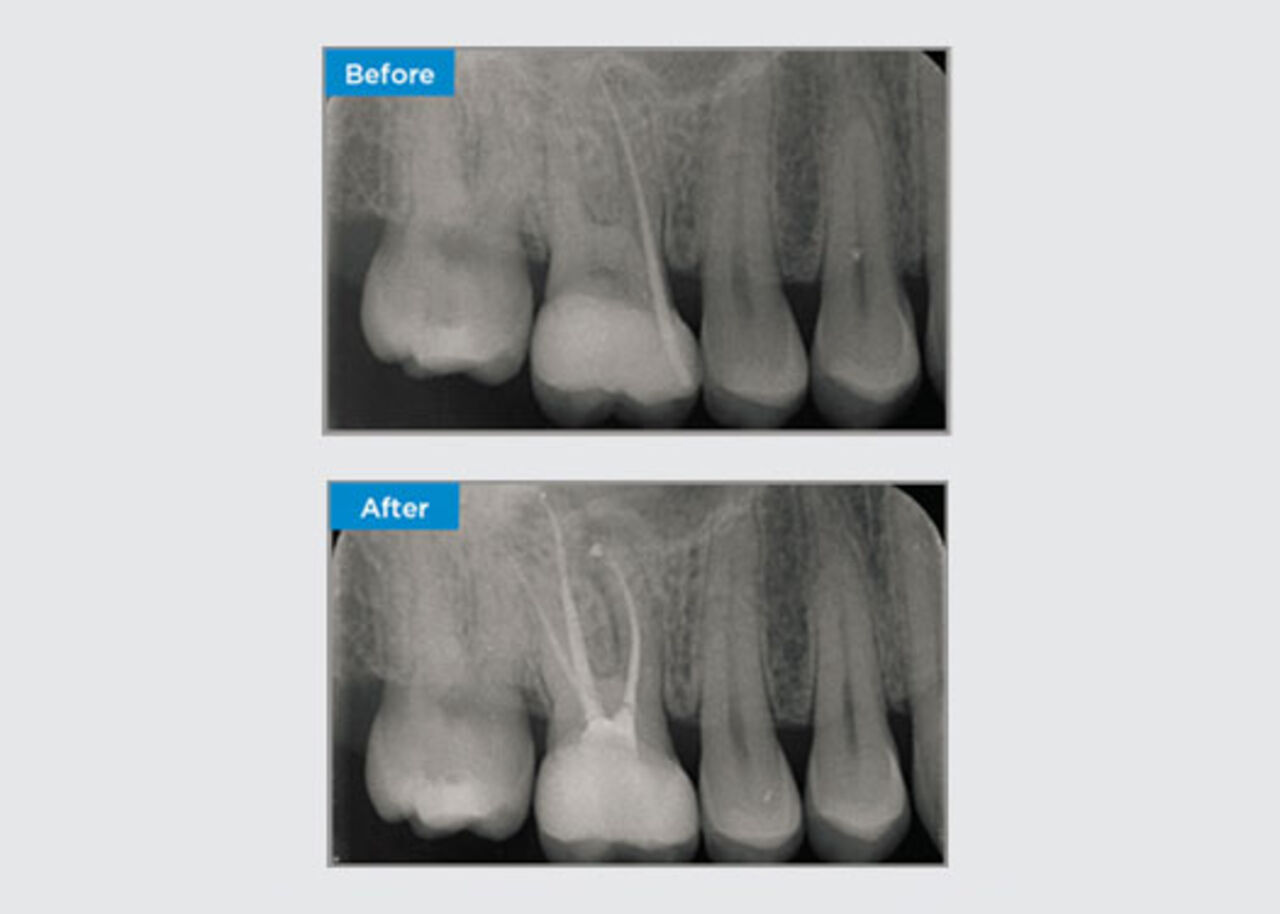

The patient presented with asymptomatic apical periodontitis on tooth 34. From the pre-op radiograph, tooth 34 was noted with two visible roots. However, a CBCT scan confirmed a three rooted premolar, and the canals divided into three at the mid root. A careful file selection is critical for this delicate tooth.

Dr Jack Lin, Endodontist, Sydney, NSW Australia

In this situation, tooth/root structure preservation is essential to reduce the risk of ledging, transportation, zipping, perforation, and root fracture. Case selection, diagnosis, and pre-treatment planning are important. Endodontic file selection with flexibility, efficiency, and respect of natural root anatomy is critical.